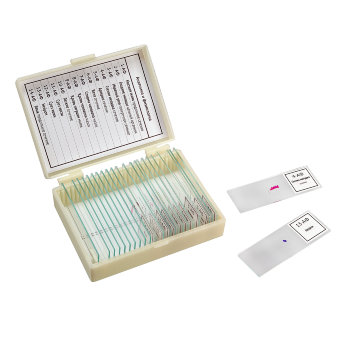

Набор микропрепаратов Konus – это 25 образцов, которые можно изучать под микроскопом. Никакой специальной подготовки не требуется: каждый препарат уже помещен на предметное стекло, обработан специальным раствором и закрыт покровным стеклом. Этот набор микропрепаратов посвящен анатомии и позволит узнать о том, как устроено человеческое тело.

Набор микропрепаратов Konus – прекрасное дополнение к микроскопу любой марки.

- Комплект из 25 специальным образом подготовленных образцов

- Каждый микропрепарат снабжен уникальным номером и имеет подпись на 8 языках

- Набор поставляется в удобной и прочной коробочке